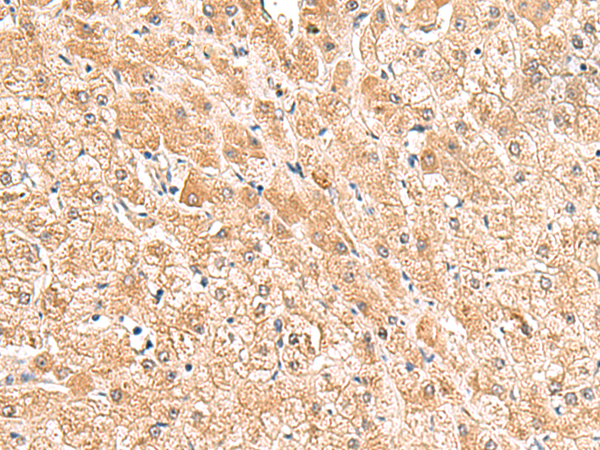

分类: 科研抗体货号: P10113别名: EIF2B; EIF-2Bbeta应用: IHC反应种属: Human, Mouse, Rat